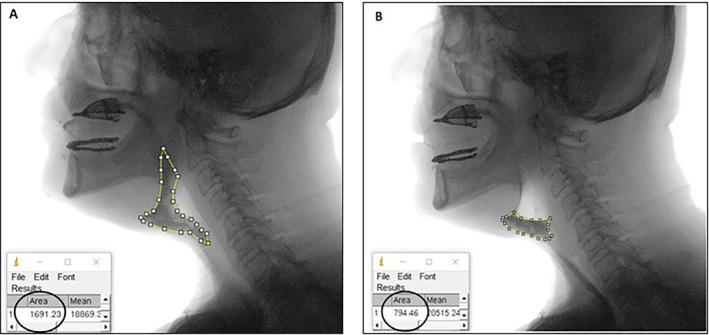

A total of 34 subjects with TL were included in the study. Swallowing kinematics of those with symptomatic swallowing complaints (Group 1) were compared to those without (Group 2). Kinematic parameters including pharyngeal transit duration (PTD), maximum pharyngeal constriction ratio (MPCR), upper esophageal sphincter opening ratio (UESOR), upper esophageal sphincter opening duration (UESOD), and bolus clearance ratio (BCR) were investigated from Videofluoroscopic Swallowing Study (VFSS) records via ImageJ software.

本研究共纳入34例全喉切除术患者。将有吞咽症状性主诉的患者(第1组)的吞咽运动学与无此主诉的患者(第2组)进行比较。通过ImageJ软件从视频荧光吞咽造影研究(VFSS)记录中调查包括咽部通过时间(PTD)、最大咽部收缩率(MPCR)、食管上括约肌开放率(UESOR)、食管上括约肌开放持续时间(UESOD)和食团清除率(BCR)在内的运动学参数。